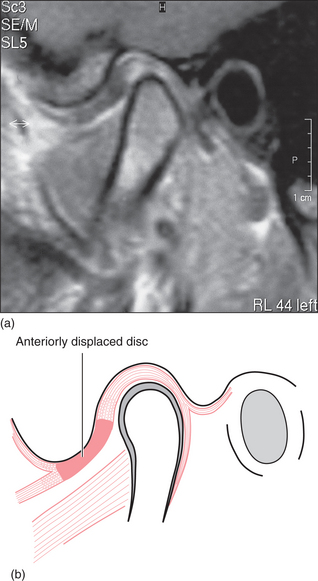

For most people with a clicking TMJ the disc is not in the position described above when the teeth are together. In these people the disc is anteriorly displaced (or anteromedially displaced). This means that the posterior ridge of the disc is actually just in front of the condyle when the teeth are in occlusion (Fig. 16.4). On mouth opening the disc displacement reduces (Fig. 16.5): the disc moves back and the condyle forward relative to each other, in a sudden movement, resulting in the click and a ‘normal’ relationship between the condyle and the disc. This anterior disc displacement with reduction has been demonstrated by cadaveric dissection, arthrography and MRI scanning as the major event associated with clicking of the TMJ. However, it is quite possible for joints without discs (such as finger joints) to click and therefore some clicks of the TMJ are probably due to other joint surface inconsistencies. When the individual with a reducing disc displacement closes their teeth together the disc is again displaced anteriorly.

image

Fig. 16.4 (a) MRI of disc displacement, mouth closed. (b) Diagram of the same.